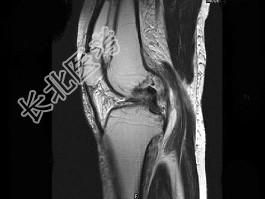

- 单项选择题女,17岁, 右膝关节有外伤史,现膝关节疼痛, 活动受限,结合图像, 最可能的诊断是 ( )

A、半月板撕裂

B、膝关节退变

C、未见异常

D、前交叉韧带断裂

E、后交叉韧带断裂